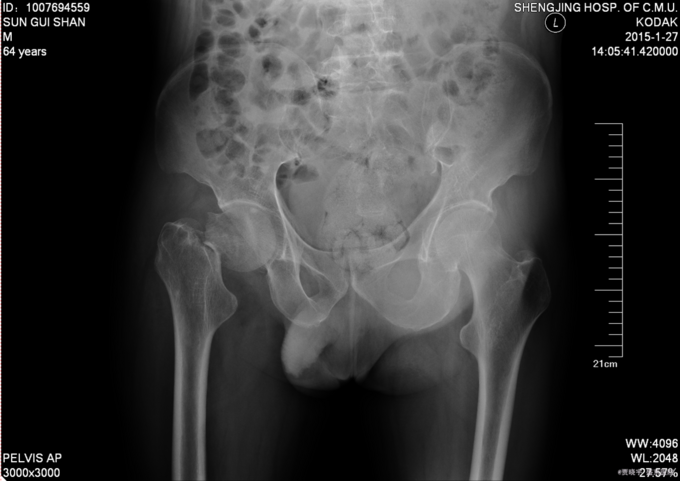

主诉:摔伤后右髋部疼痛肿胀活动受限5天。 现病史:患者男,75岁,患者家属述患者于2015-1-10日中午在自家走路时不慎摔倒,导致右大腿疼痛肿胀活动受限,无法站立行走,家人急送到当地医院,拍片检查,诊断为“右股骨颈骨折”,给予皮牵引治疗。现为求进一步治疗来我院,我科以“右股骨颈骨折”,收入院。患者自受伤以来,精神状态可,无发热,无呼吸困难,饮食睡眠正常,二便正常。

专科查体:患者平车入病房,右小腿胫骨牵引中,右下肢外展、外旋约45度,患肢缩短约1cm 右髋部疼痛,压痛(+),右下肢感觉未见异常,活动可,双侧足背动脉搏动可触及。